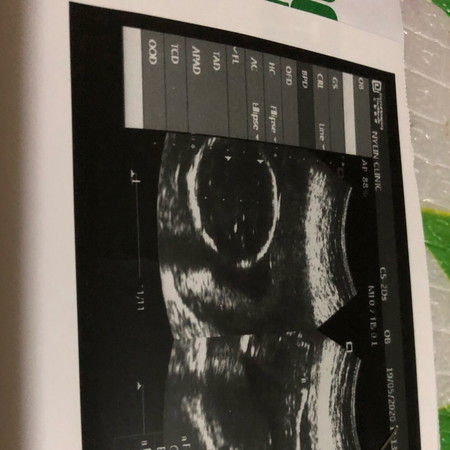

หมอบอกว่าได้ลูกชายแม่ๆช่วยดูหน่อยค่ะดูไม่ออกเลยค่ะ5555

ในภาพคือศรีษะค่ะแม่ ดูเพศไม่ได้